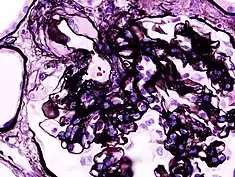

![]() Fotografía microscópica de un glomérulo lesionado consecuencia de una nefropatía diabética, la principal causa del síndrome nefrótico en adultos. | ||